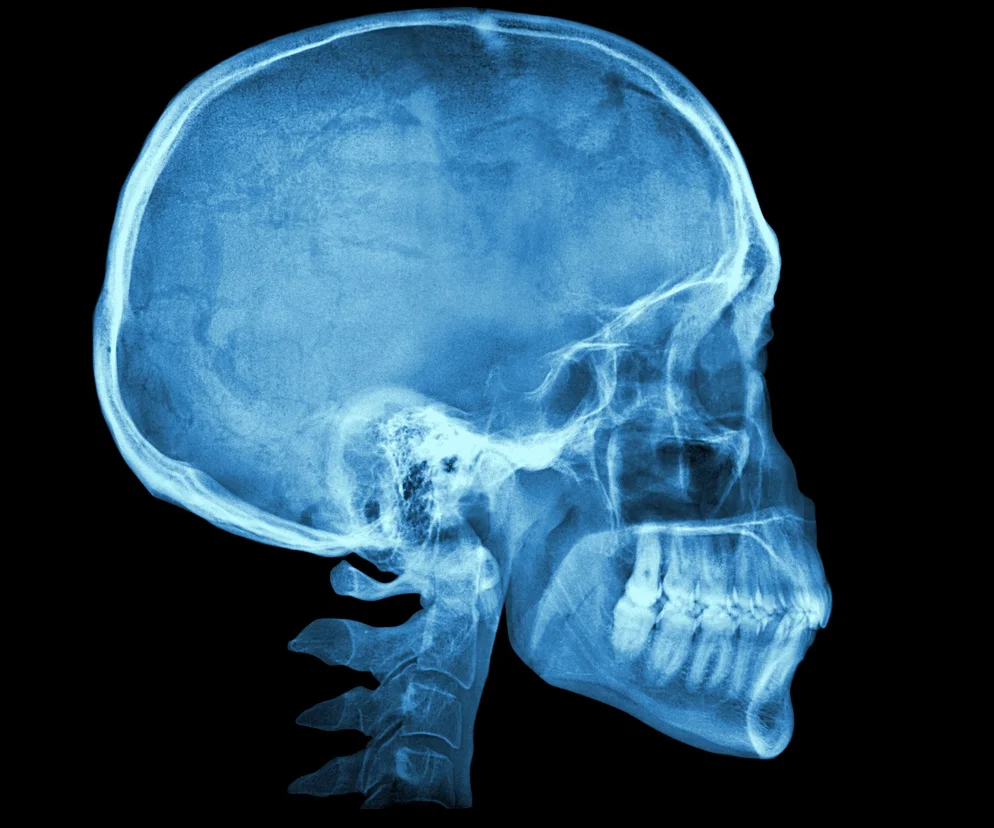

Czaszka – budowa, funkcje i złamania czaszki

Czaszka człowieka to charakterystyczna część układu szkieletowego, która odpowiada za ochronę mózgu, narządów zmysłów oraz innych tkanek znajdujących się w jej obrębie. Dzieli się na części mózgową oraz twarzową. Na wczesnym etapie rozwoju człowieka zawiera miękkie, elastyczne ciemiączka, które kostnieją po dostosowaniu się kształtu i rozmiaru czaszki do mózgowia.

Czaszka człowieka (łac. cranium) to wytrzymała struktura zbudowana z kości, które łączą się ze sobą ściśle (chrząstkozrosty, więzozrosty, szwy) oraz za pomocą stawów skroniowo-żuchwowych. Solidna, a jednocześnie lekka, w pewnym zakresie elastyczna i dość skomplikowana (pełna licznych otworów) konstrukcja czaszki może budzić podziw. Z pewnością byłaby określana wybitnym osiągnięciem inżynierii, gdyby nie fakt, że jest dziełem natury.